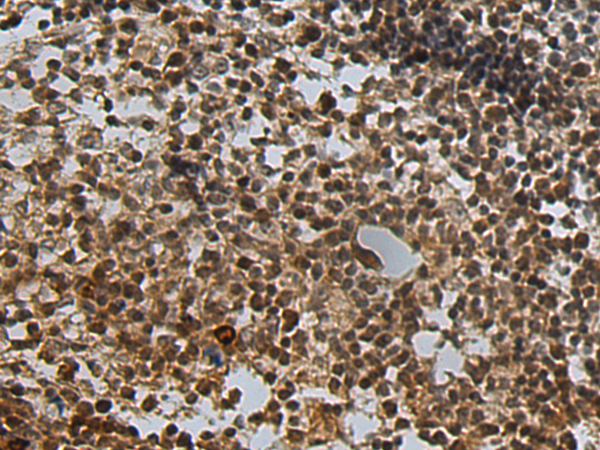

分类: 科研抗体货号: P09868别名: HPRT; HGPRT应用: WB,IHC反应种属: Human, Mouse, Rat